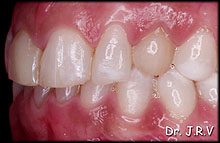

Foto

5B.- Vista lateral derecha en la que se aprecia el canino superior temporal

derecho. |

Foto 5C.- Vista lateral izquierda en la que se aprecia el canino superior temporal

Foto 5E.- Vista lateral derecha con carillas en 11,12 y 53. |

Foto 5F.- Vista lateral izquierda con carillas en 21, 22 y 63. |